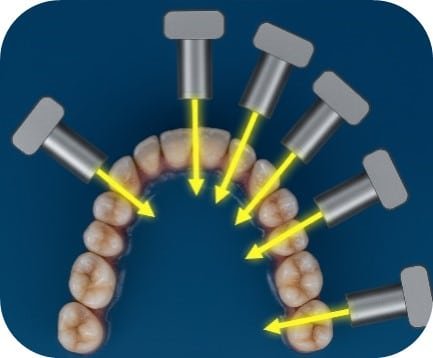

Two major techniques for periapical radiographs

- The Bisecting Angle Technique

- The Paralleling Technique

The Bisecting Angle Technique – Why Choose the Bisecting Angle?

- Ideal for Angled Teeth: When the tooth is tilted, paralleling is difficult. Bisecting compensates and still captures an acceptable image.

- Simple and Fast: Useful in emergency or time-sensitive situations.

- No Special Equipment Needed: Uses standard X-ray tools with accurate positioning.

Step 3: Aim the X-ray Beam

Objective: Direct the X-ray beam perpendicular to the bisector for an accurate image.

Key Point

- Incorrect angulation leads to elongation (too long) or foreshortening (too short).

Step 4: Adjust the X-ray cone (vertical angle)

The vertical angle refers to the up-and-down direction of the beam. It helps avoid elongation or foreshortening.

Why Adjust the Vertical Angle?

- Elongation occurs if the vertical angle is too small.

- Foreshortening occurs if the vertical angle is too large.